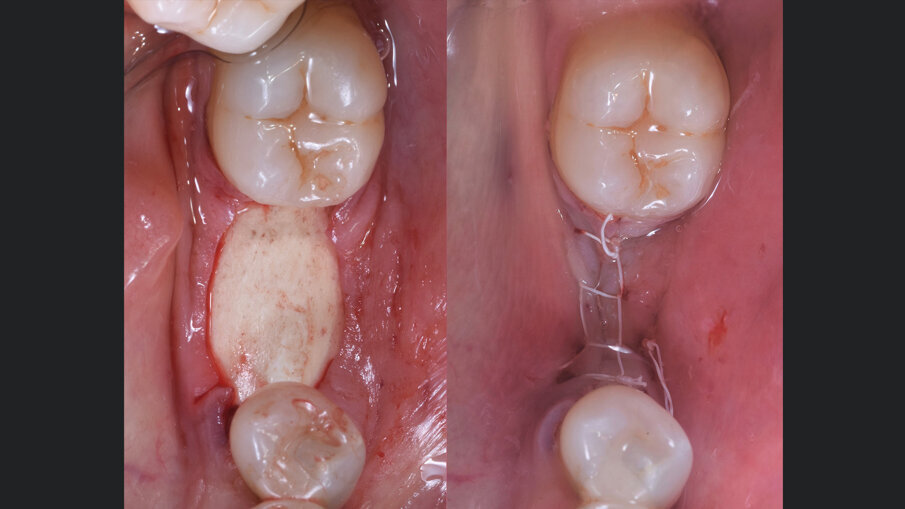

Il giorno prima dell’intervento, la paziente veniva sottoposta a terapia antibiotica con Amoxicillina e Acido Clavulanico compresse da 1 gr ogni 12 ore. Il giorno dell’intervento veniva eseguita la profilassi antibiotica 1 ora prima dell’inizio con 1 g di Amoxicillina più Acido Clavulanico e veniva praticata l’anestesia locale con Articaina più adrenalina 1:200.000. All’apertura del lembo veniva confermata clinicamente l’atrofia orizzontale a livello dell’elemento 36 (Fig. 2). Il sito veniva opportunamente gestito. L’innesto veniva preparato inizialmente miscelando i granuli cortico-spongiosi a collagene preservato con il gel osteopromozionale in rapporto 1:1, andando a formare un conglomerato adesivo che facilita la successiva apposizione. Tale procedura permette, al contempo, di idratare l’innesto e di aumentarne il potenziale rigenerativo, in virtù della presenza di matrice ossea demineralizzata. Parallelamente, la lamina corticale flessibile veniva idratata per 10 secondi in soluzione salina tiepida (Figg. 3, 4). Infine, l’innesto eterologo veniva caricato sulla lamina corticale flessibile pre-idratata con la tecnica del “taco” e quindi inserita a colmare l’atrofia orizzontale (Fig. 4). I lembi venivano chiusi con delle suture in PTFE 4.0 per favorire la guarigione per prima intenzione (Fig. 4). A 6 mesi dalla GBR, l’aspetto clinico mostrava un’ottima guarigione dei tessuti molli e un notevole incremento orizzontale della cresta alveolare. All’apertura si evidenziava la risoluzione dell’atrofia orizzontale e l’innesto eterologo completamente sostituito da osso neoformato e sanguinante alla sua perforazione (Fig. 5).

Fig. 1 - Aspetto clinico dell’atrofia orizzontale a livello dell’elemento 36 estratto alcuni anni prima.

Fig. 5 - A sinistra, l’aspetto ottimale dei tessuti molli a 6 mesi dalla GBR. A destra, la riapertura che mostra la risoluzione dell’atrofia orizzontale e il rimodellamento completo dell’innesto eterologo con osso neoformato.